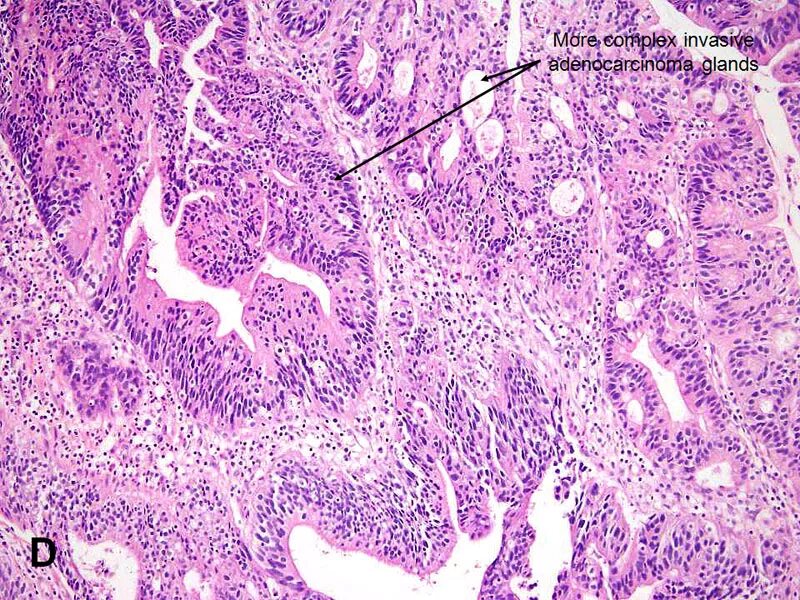

Гистология аденокарциномы